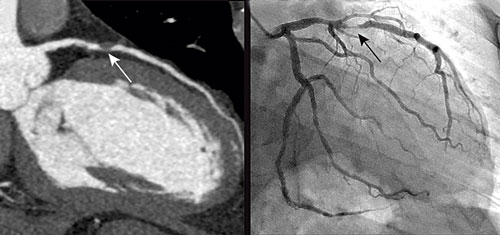

Till vänster: Datortomografiundersökning av kranskärl hos en 51-årig man med angina pectoris. Vit pil visar tät stenos i vänster koronarartärs främre nedåtstigande gren (LAD). Till höger: Traditionell kranskärlsröntgen hos samma patient. Svart pil visar samma stenos som bilden till vänster.